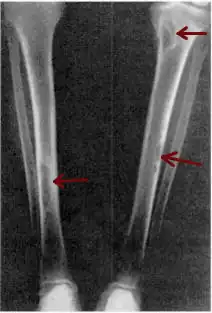

X-ray of a pair of human tibia, which run from the top right and left corner of the image into the bottom center, where they almost converge. Small gray blemishes, identified as brown tumors, can be seen at the top and halfway down the right tibia and about three-quarters down the length of the left tibia.

Osteitis fibrosa cystica of the tibia. Arrows point to the brown tumors which are typically present in bones of people with OFC.